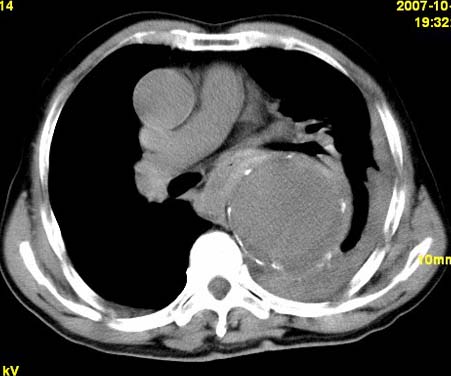

标题: CT10190:男,70,胸部疼痛数年,加重一天。典型病例。 [打印本页]

标题: CT10190:男,70,胸部疼痛数年,加重一天。典型病例。

考虑胸主动脉瘤破裂,胸腔积液

主动脉夹层

胸主动脉瘤破裂,胸腔积液,胸膜肥厚

支持:降主动脉瘤!破裂?胸腔积液。

胸主动脉瘤破裂,胸腔积液